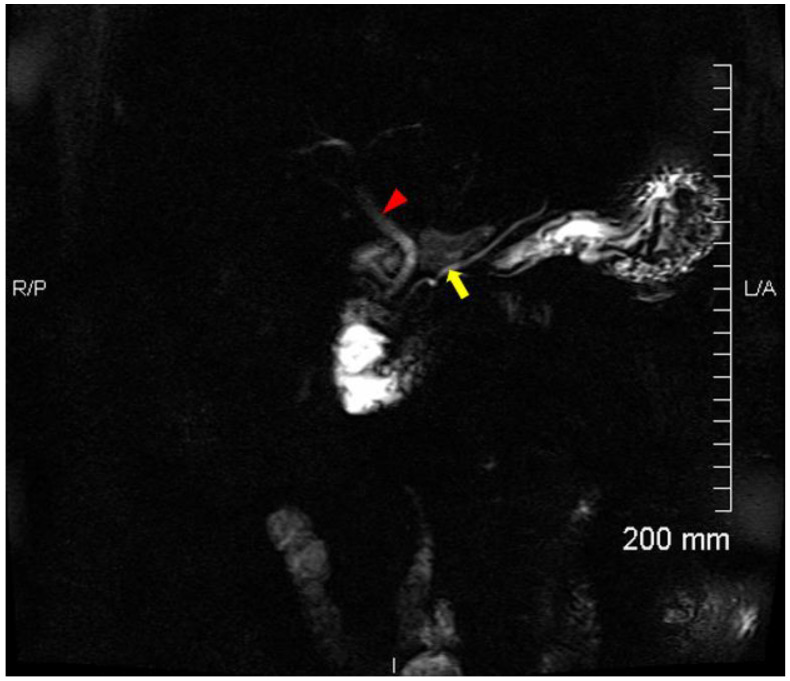

Due to incidental CT findings of a left upper lobe pulmonary nodule, an [18F] FDG positron emission tomography (PET) was performed approximately one month post-ERCP. In addition to a moderately hypermetabolic left upper lobe pulmonary nodule, which was later proven to be a metastasis from colon cancer, there were incidental findings of increased uptake in the CBD, with a SUVmax of 13.3, suspicious for cholangitis (Figure 2). A follow-up magnetic resonance cholangiopancreatography (MRCP) was performed 9 days after the [18F] FDG PET showed no evidence of cholangitis, pancreatitis, or choledocholithiasis (Figure 3).

Cholangitis is an inflammation of the bile duct. Acute cholangitis occurs most commonly from bacterial infection of the bile ducts, characterized by fever, jaundice, and abdominal pain (Charcot’s triad), which in most cases is a consequence of biliary obstruction [ref. 4]. Diagnosis is commonly made by the presence of clinical features, laboratory tests, and imaging studies. At the time of [18F] FDG PET imaging, there were no clinical features suggestive of acute infectious cholangitis based on Charcot’s or the 2018 Tokyo criteria [ref. 5,ref. 6]. In addition, a follow-up MRCP 9 days post-[18F] FDG PET showed no evidence of cholangitis.